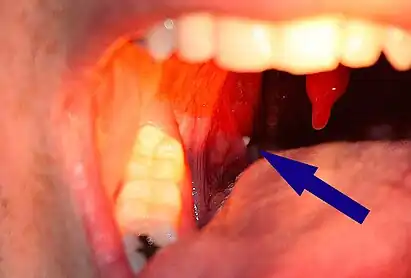

| A tonsillolith lodged in the tonsillar crypt | |

A tonsillolith protrudes from the tonsil

Large tonsillolith half exposed on tonsil

Closeup of a tonsillolith